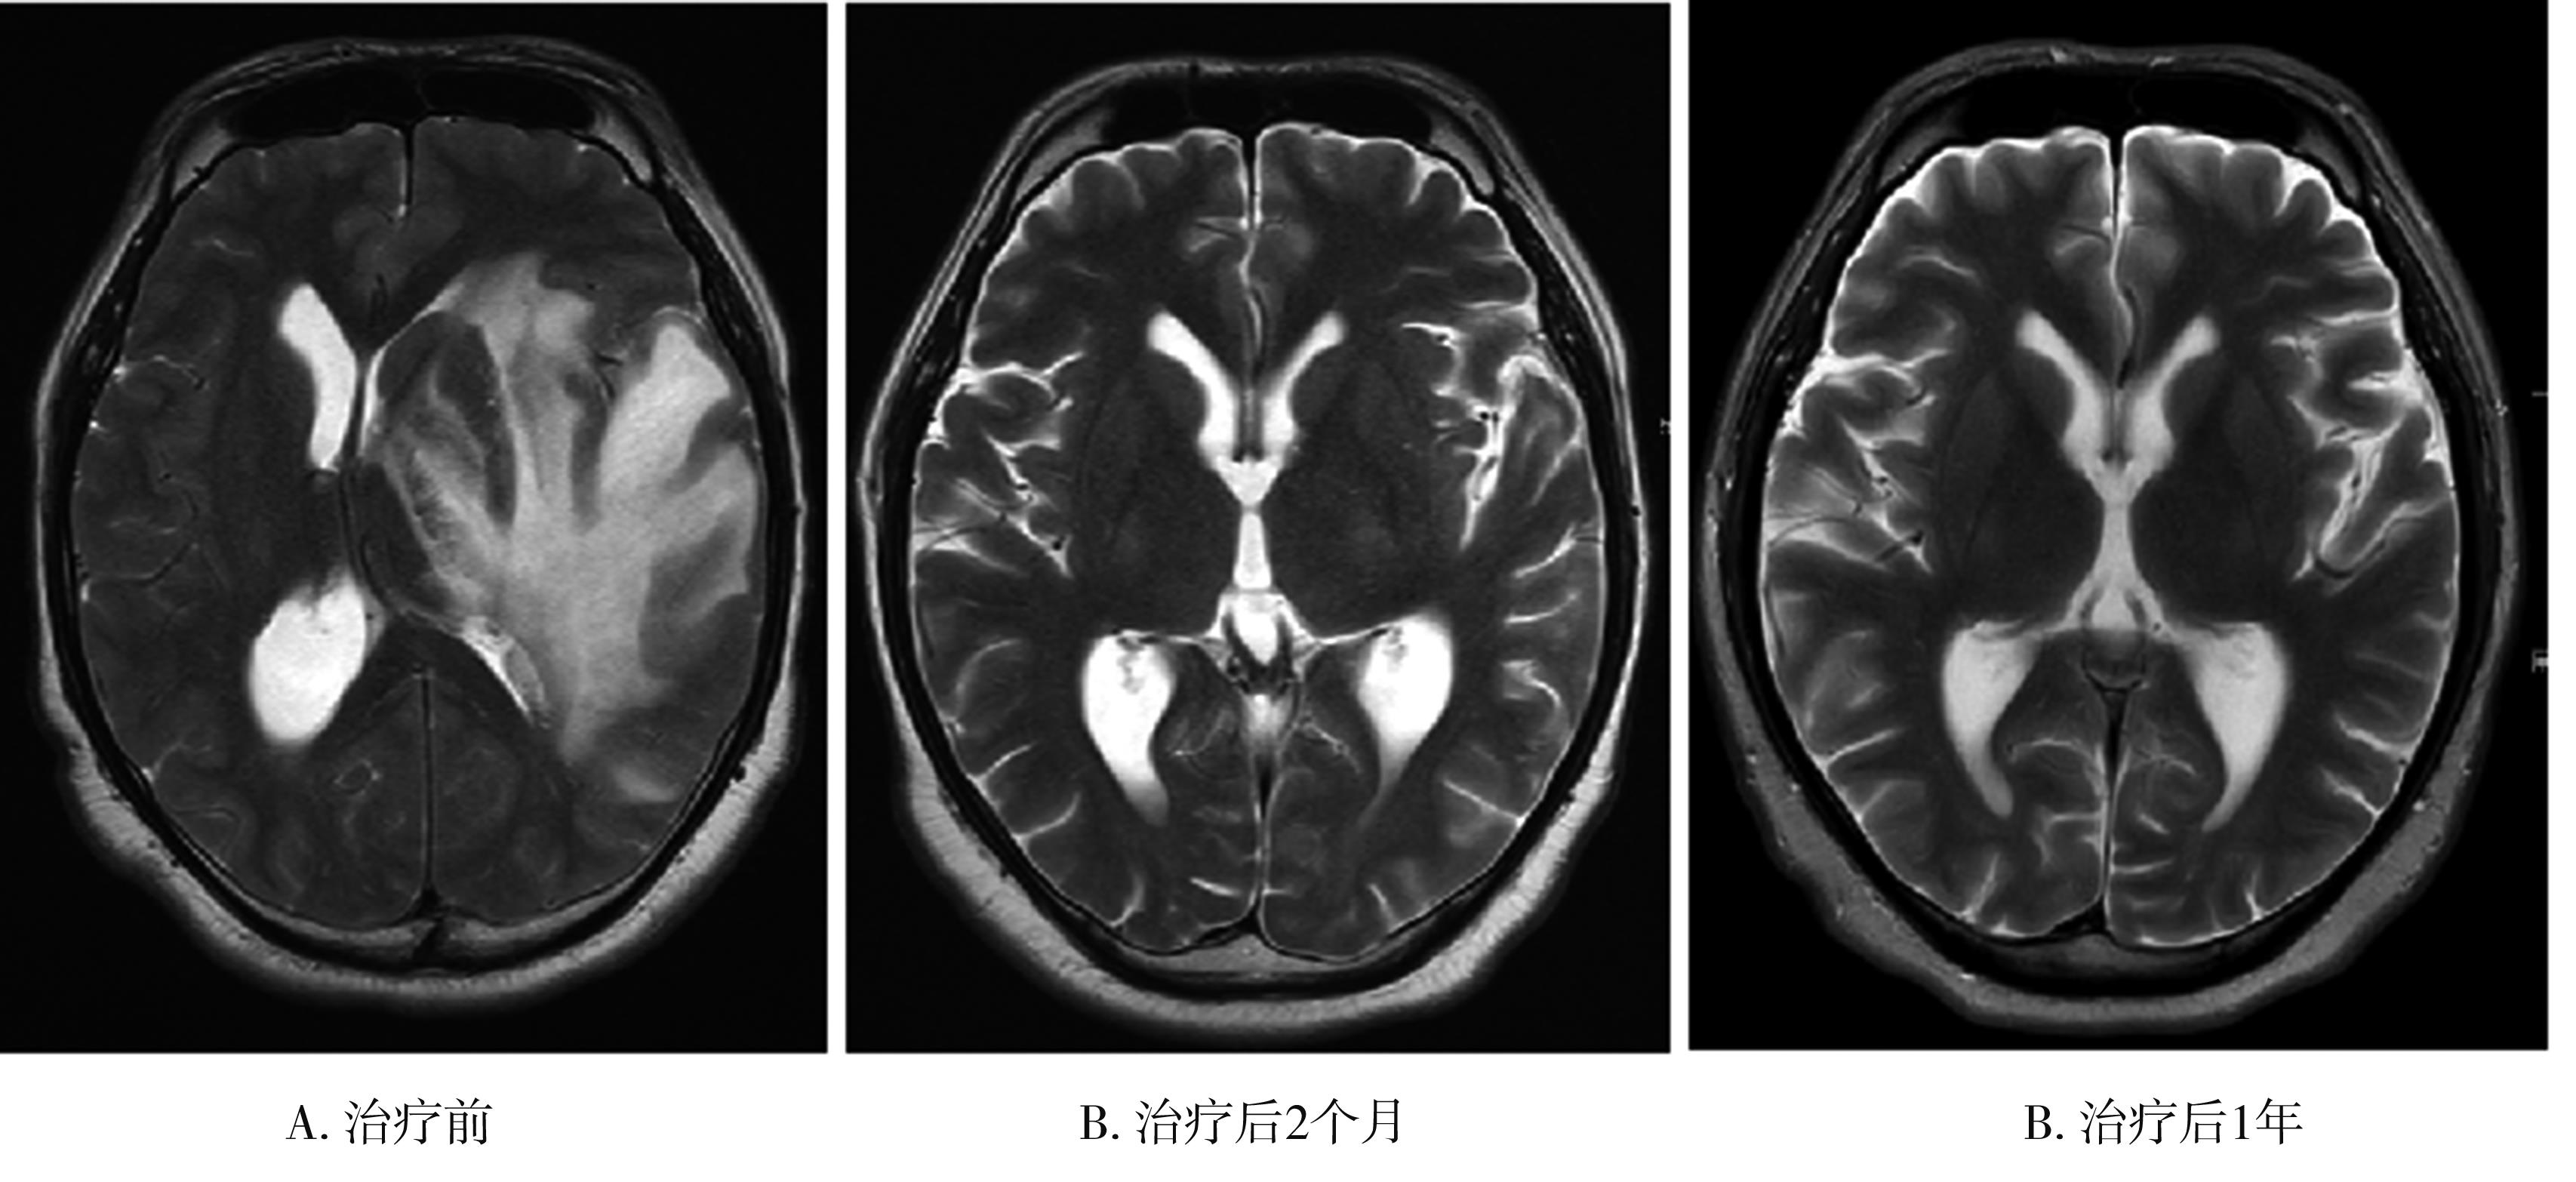

• 放射性脑损伤的治疗进展

摘要:放射治疗在控制头颈部肿瘤提高患者生存率的同时,对周围正常脑组织也造成不同程度的损伤,引起放射性脑坏死和认知功能下降,其发生率最高可达90%,严重影响患者的生活质量。研究人员近年来在多个层面上对放射性脑损伤的潜在病因进行了探索,通过筛查和鉴定不同干预靶点,为预防和治疗放射性损伤提供了新的策略。本文对放射性脑损伤的发生发展机制进行了综述,并回顾了现有的药物及非药物干预手段,提出了目前该领域面临的挑战及未来的研究方向。